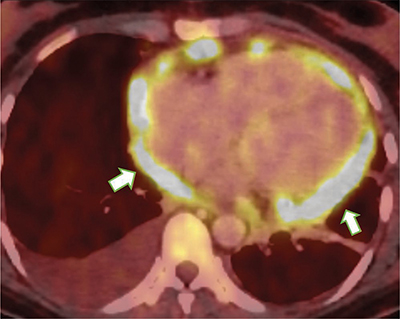

Figure 4

Nodular thickening of the pericardium with intense FDG uptake (arrows).